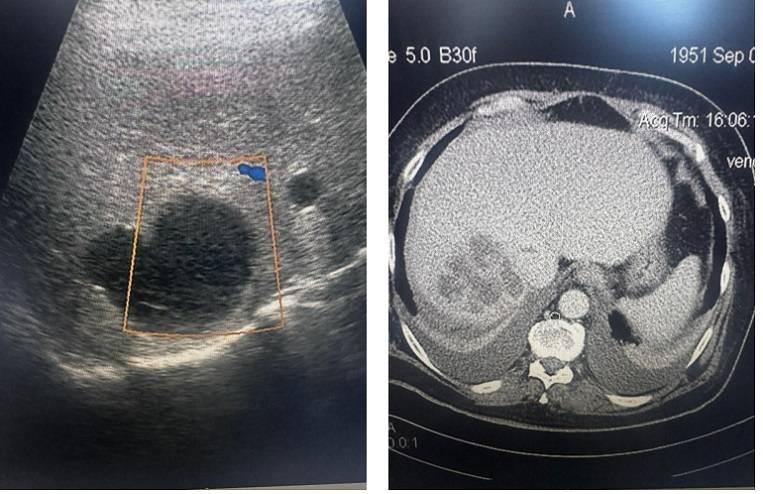

В пресс-службе Минздрава Приморья уточнили, в приёмном покое сразу провели обследование. УЗИ выявило огромную кисту, полностью закрывавшую печень — состояние требовало немедленного вмешательства.

«Под местной анестезией, под контролем УЗИ мы выбрали оптимальную точку доступа, установили дренаж и эвакуировали около двух литров жидкости из кисты. Затем ввели склерозирующие препараты — они позволяют “склеить” полость и избежать повторного заполнения», — рассказал руководитель отделения общей хирургии Игорь Кондрашов.